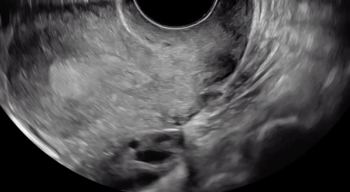

The uterine fundus is being pushed cephalad by the transvaginal ultrasound probe, eliciting smooth sliding of the uterine fundus over the bowel. Some fluid is noted within the rectouterine pouch, which often suggests a non-obliterated pouch.

In this case, there is a fixed ovary posteriorly and subtle hypoechoic nodule posterior to the uterus at the level of the internal cervical os, suggesting of deep endometriosis of the torus uterinus.